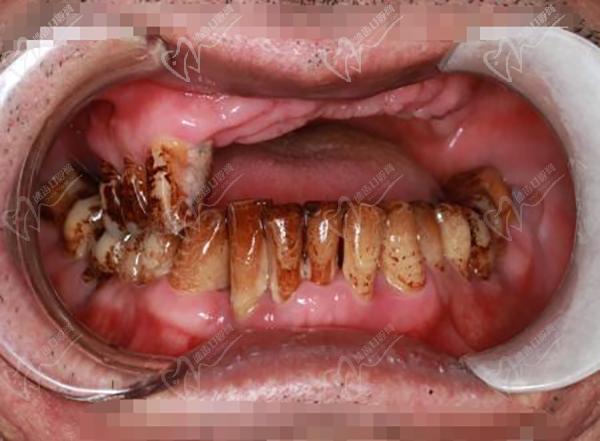

7、廣州暨博口腔醫(yī)院(體育東店):專注口腔醫(yī)療20余年,在牙齒美白、全口種植等方面技術(shù)嫻熟。